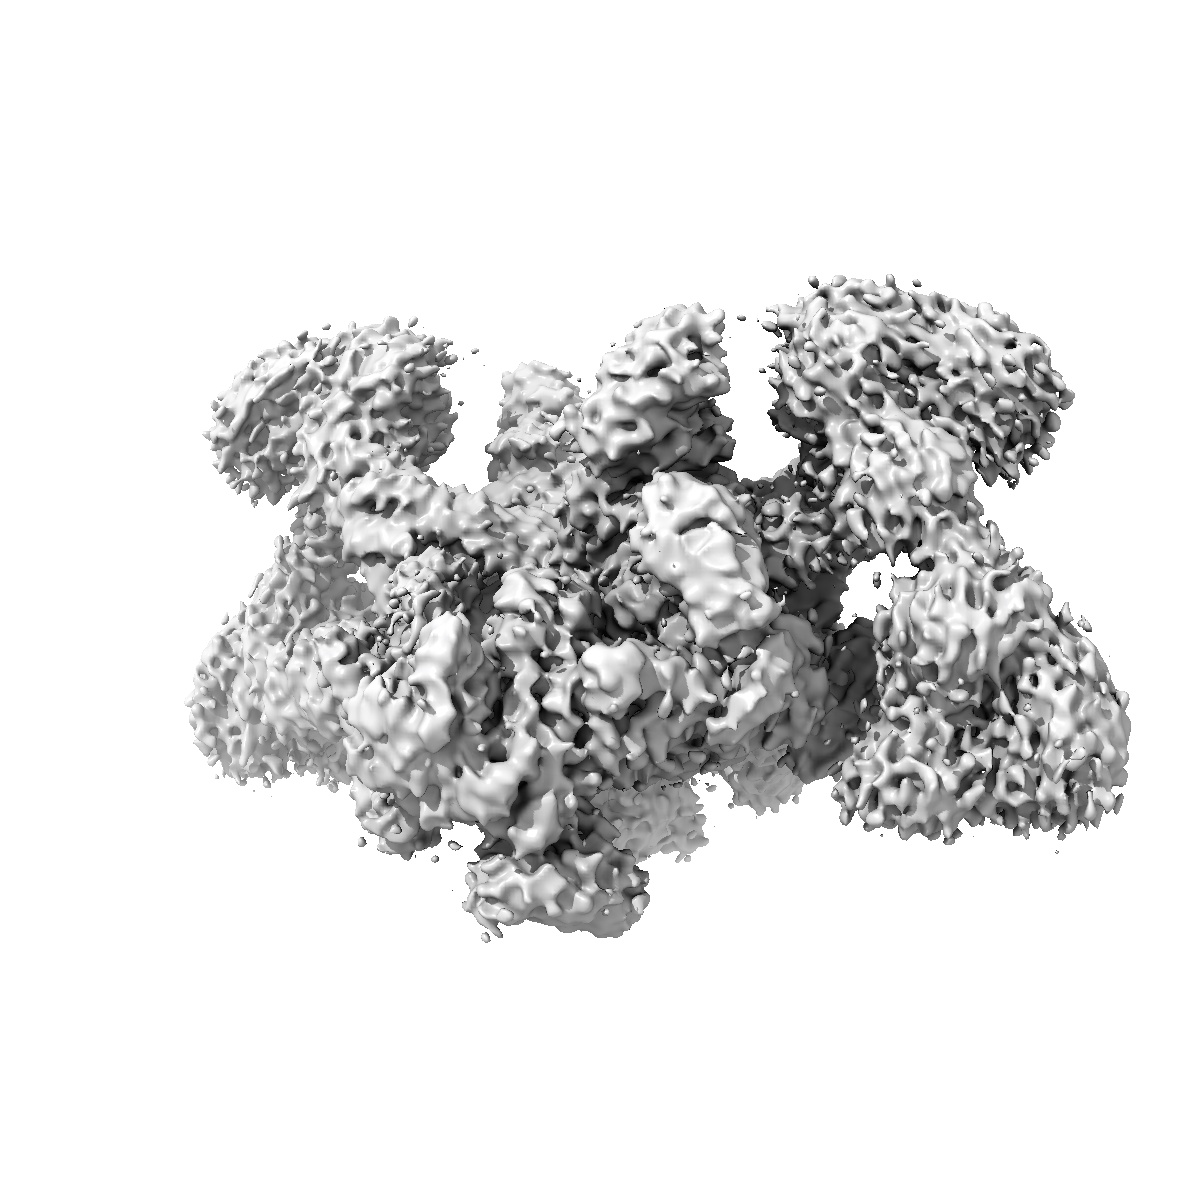

SARS-CoV-2 Replication-Transcription Complex has a dimer architecture (dRTC) in post-capping state

Sample: post capping initiation RTC

Structural basis for the concurrence of template recycling and RNA capping in SARS-CoV-2.

Yan L, Huang Y, Liu Y, Ge J, Gao S, Tan L, Liu L, Liu Z, Ye S, Wang J, Xiong J, Zhou Y, Zhao H, Zhao X, Guddat LW, Gao Y, Zhu L, Rao Z, Lou Z

(2025) Cell , 188 , 7194 - 7205.e10